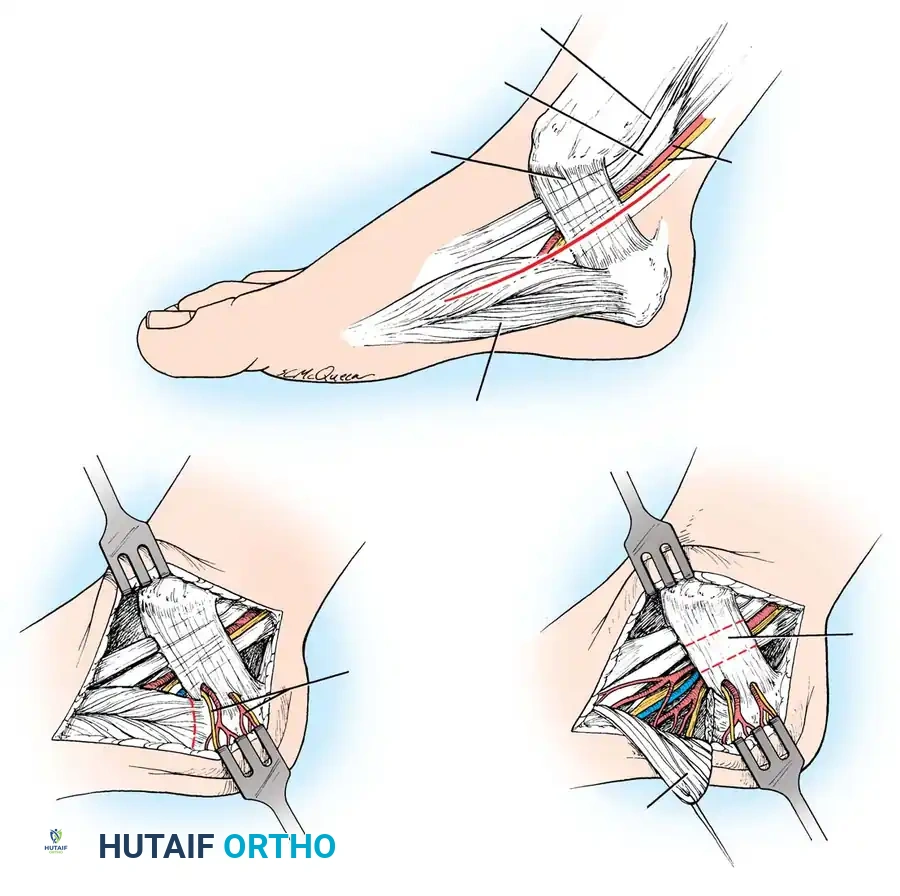

Fig 3: Surgical diagram of the Tarsal Tunnel Release. Note the trajectory of the incision and the critical relationship of the posterior tibial nerve bifurcating beneath the flexor retinaculum.

- Incision Trajectory: Begin the incision 1 cm plantar to the navicular tuberosity. Extend it proximally, bisecting the area between the medial malleolus and the medial aspect of the calcaneal tuberosity. Curve the incision gently to end 1 cm anterior to the Achilles tendon. With the foot held in gravity equinus, this forms an almost straight line.

- Tissue Handling: Do not undermine the skin edges to preserve the fragile subdermal vascular plexus.

Step 3: Retinaculum Release and Nerve Decompression

- Proximal Release: Begin by incising 1 to 2 cm of the deep investing fascia of the calf proximal to the upper edge of the flexor retinaculum. The nerve is occasionally enlarged or pseudoneuromatous at this proximal entry point.

- Unroofing the Tunnel: Using small dissecting scissors and non-toothed forceps, release the flexor retinaculum from a proximal to a distal direction.

- Protecting the Medial Calcaneal Nerve: Exercise extreme vigilance for the medial calcaneal branch(es). These may arise from the main tibial nerve or the lateral plantar nerve and frequently penetrate directly through the retinaculum. Severing these branches will result in a debilitating, painful neuroma.

Step 4: Distal Dissection and Branch Tracking

- Continue the release distally until the muscle fibers of the abductor hallucis are reached.

- The tibial nerve will divide into the medial and lateral plantar branches. Follow both the medial and lateral plantar nerves beneath the deep fascia of the abductor hallucis muscle.

- Fascial Slings: One or both of these branches may pass through tight fascial slings as they dive into the plantar surface of the foot. These slings must be completely released to ensure total decompression.